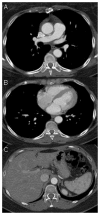

Uterine intravenous leiomyomatosis is an uncommon tumor, usually arising from the uterus, with nodular masses which extend intravascularly over variable distances and may reach the inferior vena cava, right atrium, and pulmonary arteries. Early diagnosis and surgical intervention are crucial as intracardiac leiomyomatosis not only causes cardiac symptoms but may result in pulmonary embolism and sudden death. Complete tumor resection is key in disease management, thus rendering cardiac-extending uterine intravenous leiomyomatosis one of the most challenging conditions for surgical treatment. The use of interventional radiology procedures can facilitate the surgical approach. We report the case of a massive pelvic recurrence of uterine leiomyomatosis with intracardiac extension and pulmonary embolism, analyzing management and surgical outcomes, highlighting the role of interventional radiology during the therapeutic pathway. Nonetheless, there are currently very few data available concerning the use of interventional radiology procedures in the therapeutic strategy of uterine intravenous leiomyomatosis with intracardiac extension.